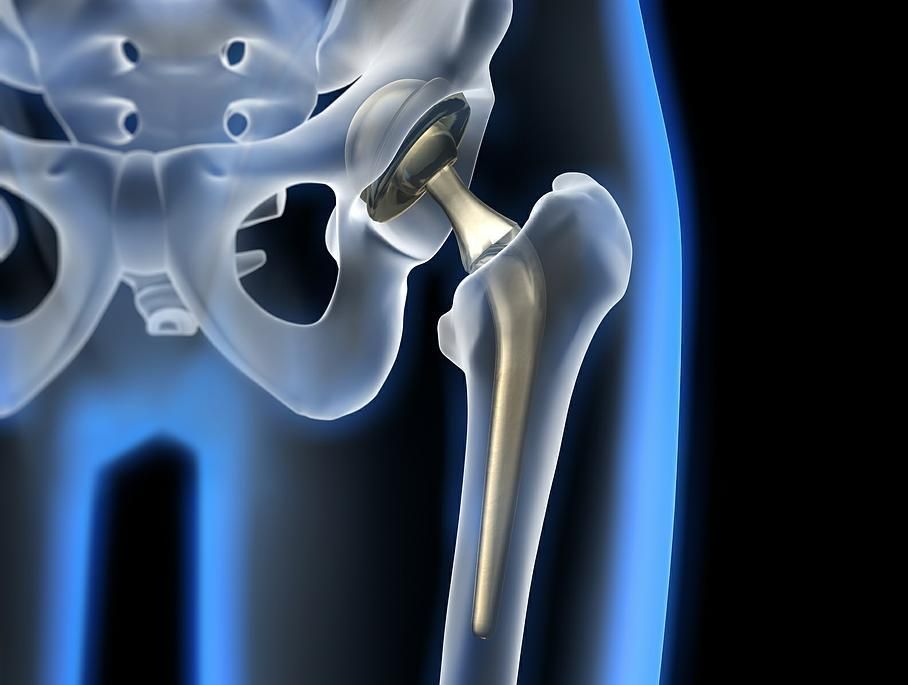

Arthrose de la hanche, ou coxarthrose:

L’évolution d’une arthrose de la hanche se fait par usure du cartilage et apparition de douleurs qui deviennent handicapantes pour la personne. Une fois le cartilage abîmé, il n’existe pas de solution médicale pour le reconstituer.

Dès lors, un remplacement de l’articulation par une articulation artificielle, nommée prothèse, s’avère nécessaire. Ceci se fait par une intervention chirurgicale, dite mini-invasive, en préservant les muscles et les tendons. L’opération se fait quand les douleurs surviennent à la marche, et des fois la nuit, et qu’elles ne sont plus soulagées par aucun traitement médical.

Il peut donc s’écouler plusieurs années entre la découverte de l’arthrose de la hanche et la mise place d’une prothèse. L’intervention permet de rétablir une marche indolore et de reprendre certaines activités sportives. Le taux de satisfaction des patient(e)s est très élevé.